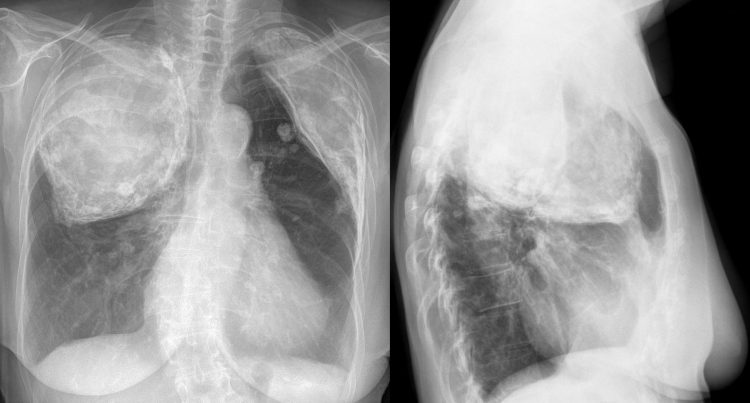

„Judeţul Maramureş a intrat într-un nou program de tuberculoză, care va însemna o deplasare în teritoriu a colegilor mei, inclusiv cu un aparat de radiologie mobilă, pentru a veni mult mai aproape de nevoile pacienţilor”, a detaliat Rareş Pop.